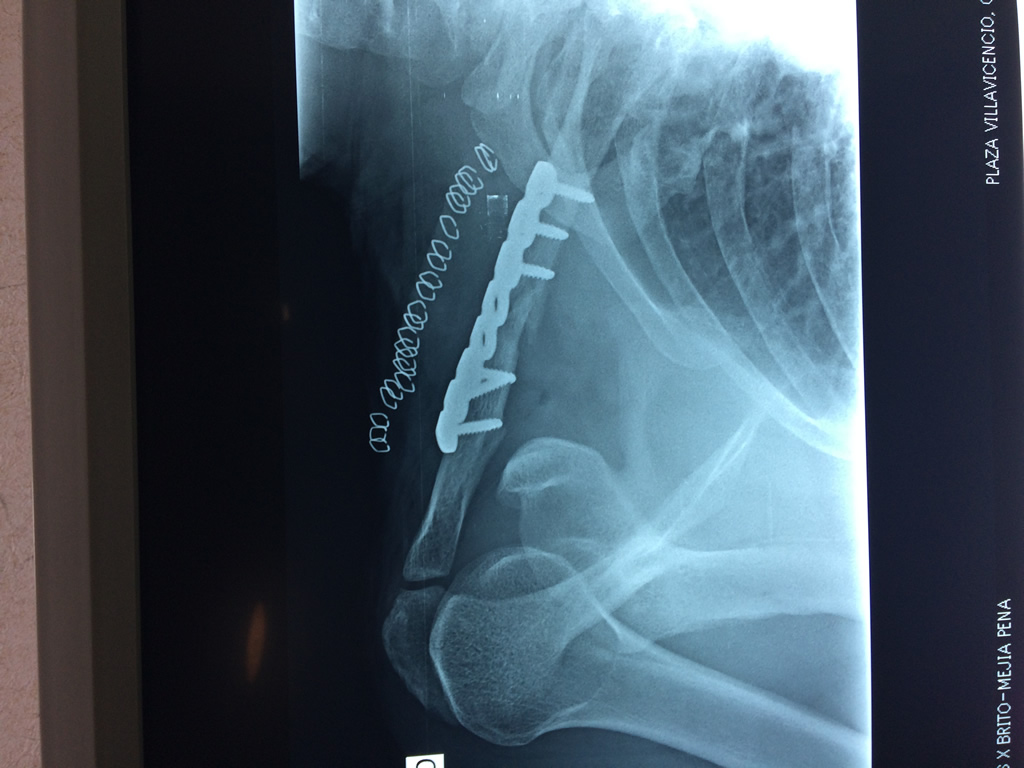

Se considera el único medio de unión entre el miembro superior y el tórax. A pesar de su aspecto, similar al de un hueso largo, posee una estructura semejante a la de un hueso plano, ya que carece de epífisis y de diáfisis, lo que la harían entrar dentro de la clasificación de hueso largo. Carece de un canal medular propiamente dicho.